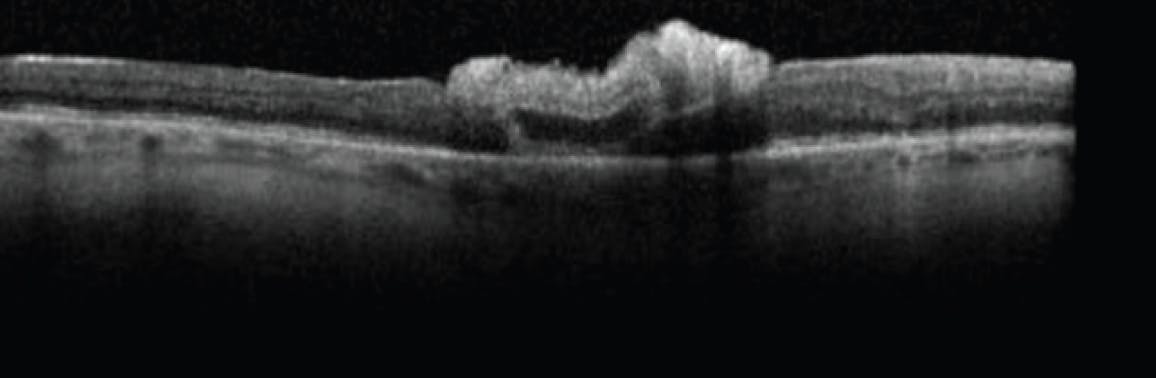

The patient was eager to undergo a second attempt, which was performed 1 week later. Imaging obtained 1 day after the second ART procedure showed the hole to be adequately covered by the graft under PFO tamponade (Figure 3). His VA was 3/200 OD. Repeat OCT demonstrated an adequately positioned graft and closed macular hole (Figure 4).

<p>Figure 4. OCT imaging 1 day after the second procedure depicted the graft in an adequate position and a closed macular hole.</p>

Figure 4. OCT imaging 1 day after the second procedure depicted the graft in an adequate position and a closed macular hole.